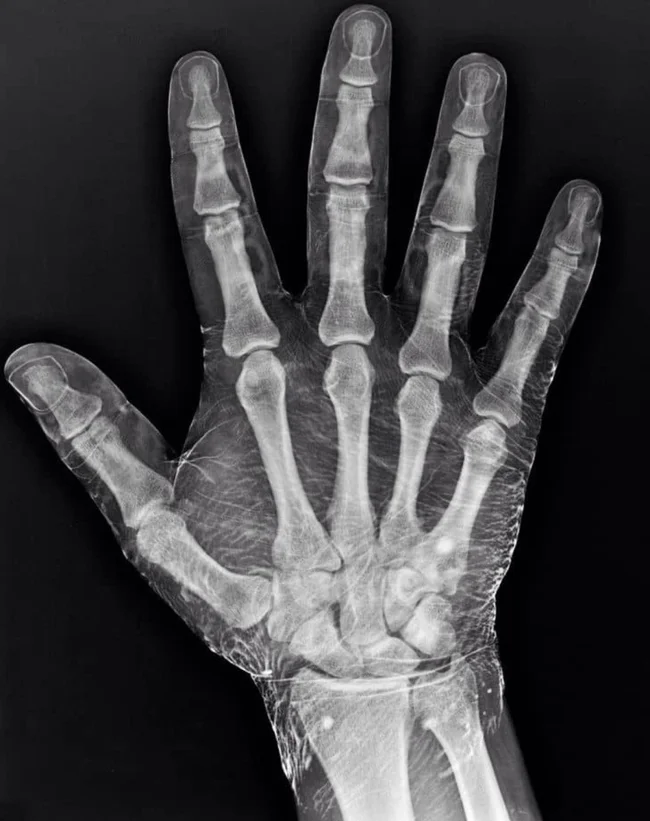

Рентгенограмма руки, которую обмакнули в йод. Он сработал как контрастное вещество